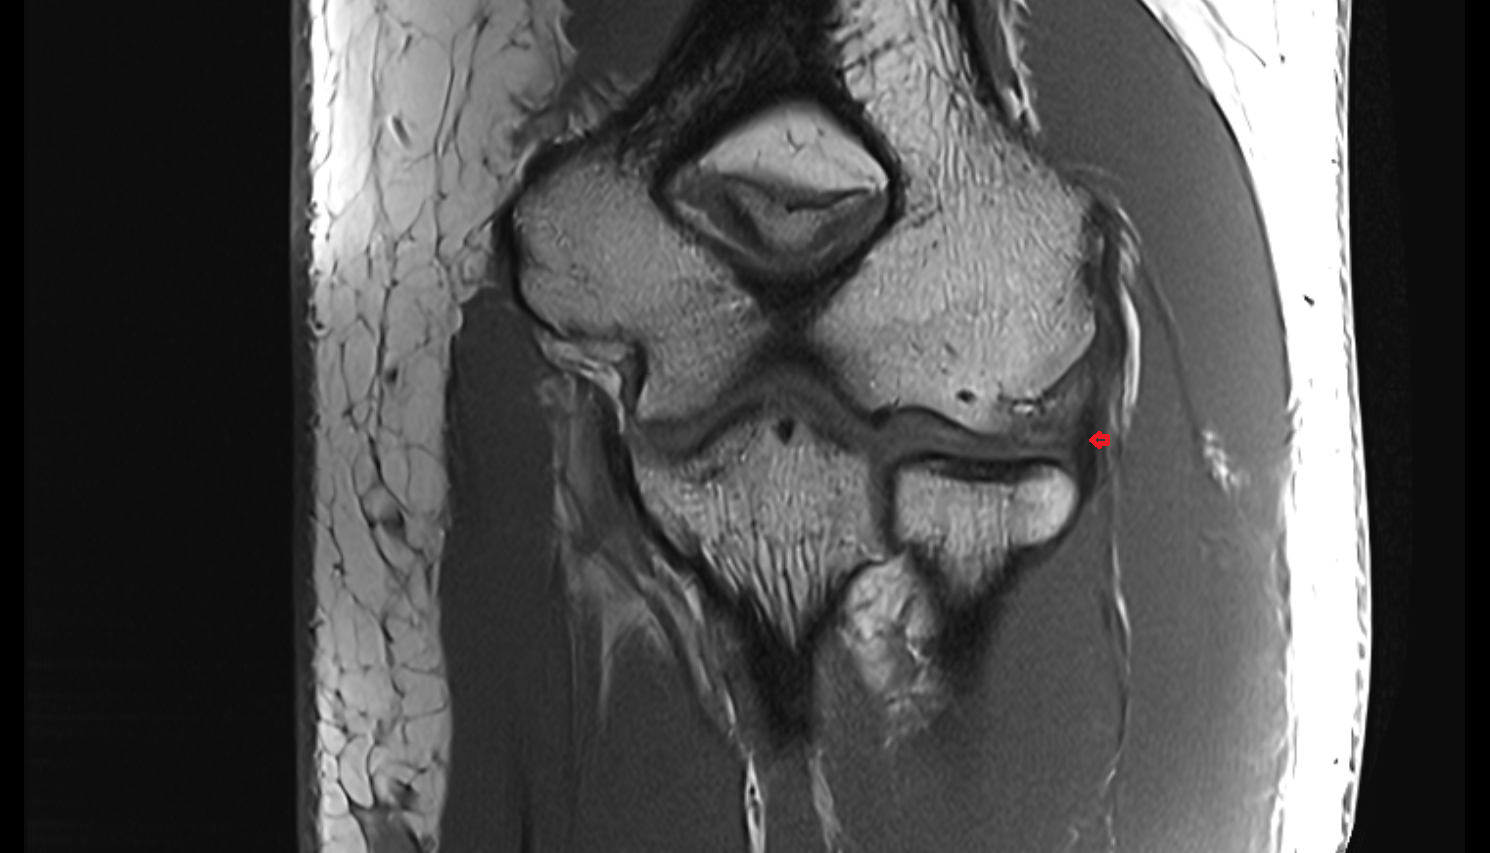

- Medial collateral ligament

- Medial meniscus

- Lateral meniscus